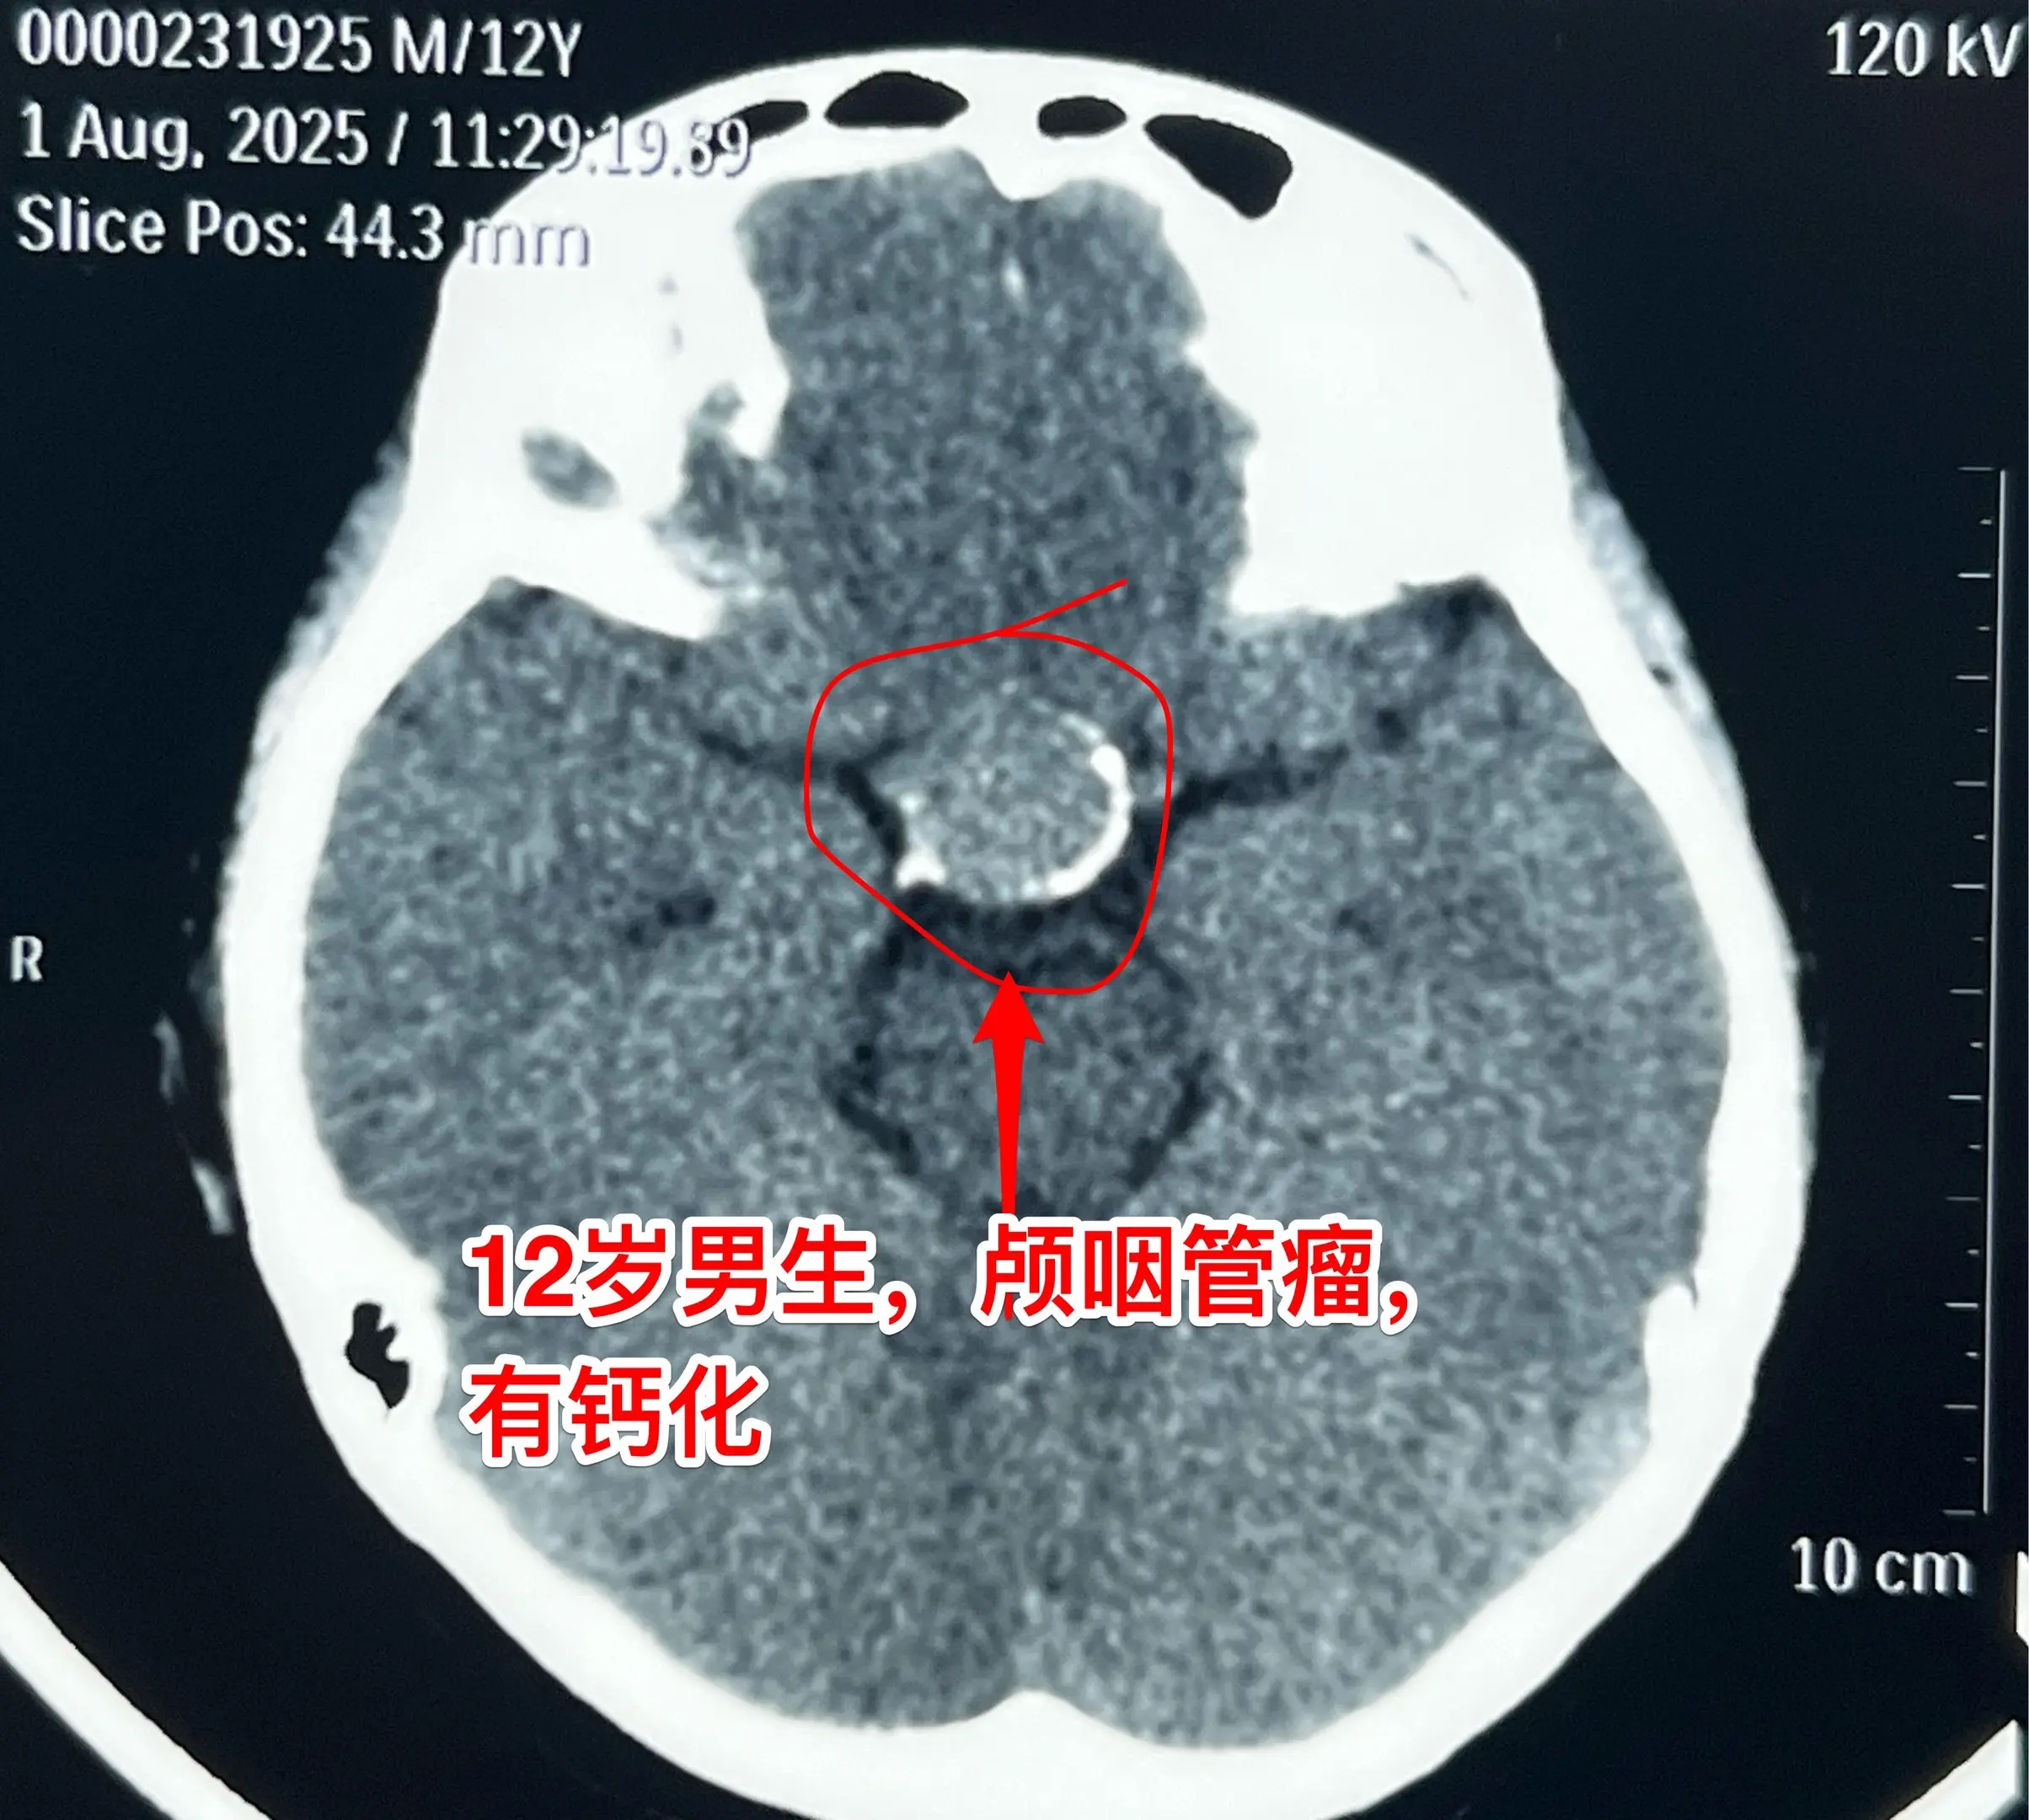

12岁男孩子,视力差、身高增长缓慢。12岁男孩子,视力下降、身高增长缓慢。头CT及MRI显示为典型的造釉型颅咽管瘤。2025年8月7日作了开颅手术。 根据术前的CT和MRI无法判断出垂体受压程度、能否保留垂体和垂体柄。 手术中发现垂体受肿瘤压迫成薄片状,如同饺子皮。好在肿瘤与垂体粘连不紧,经过细心分离,将肿瘤完全切除,同时垂体柄-垂体保留约90%(垂体前叶和后叶均保留)。 这样保留垂体柄和垂体是有意义的,可以减少垂体危象的发生。